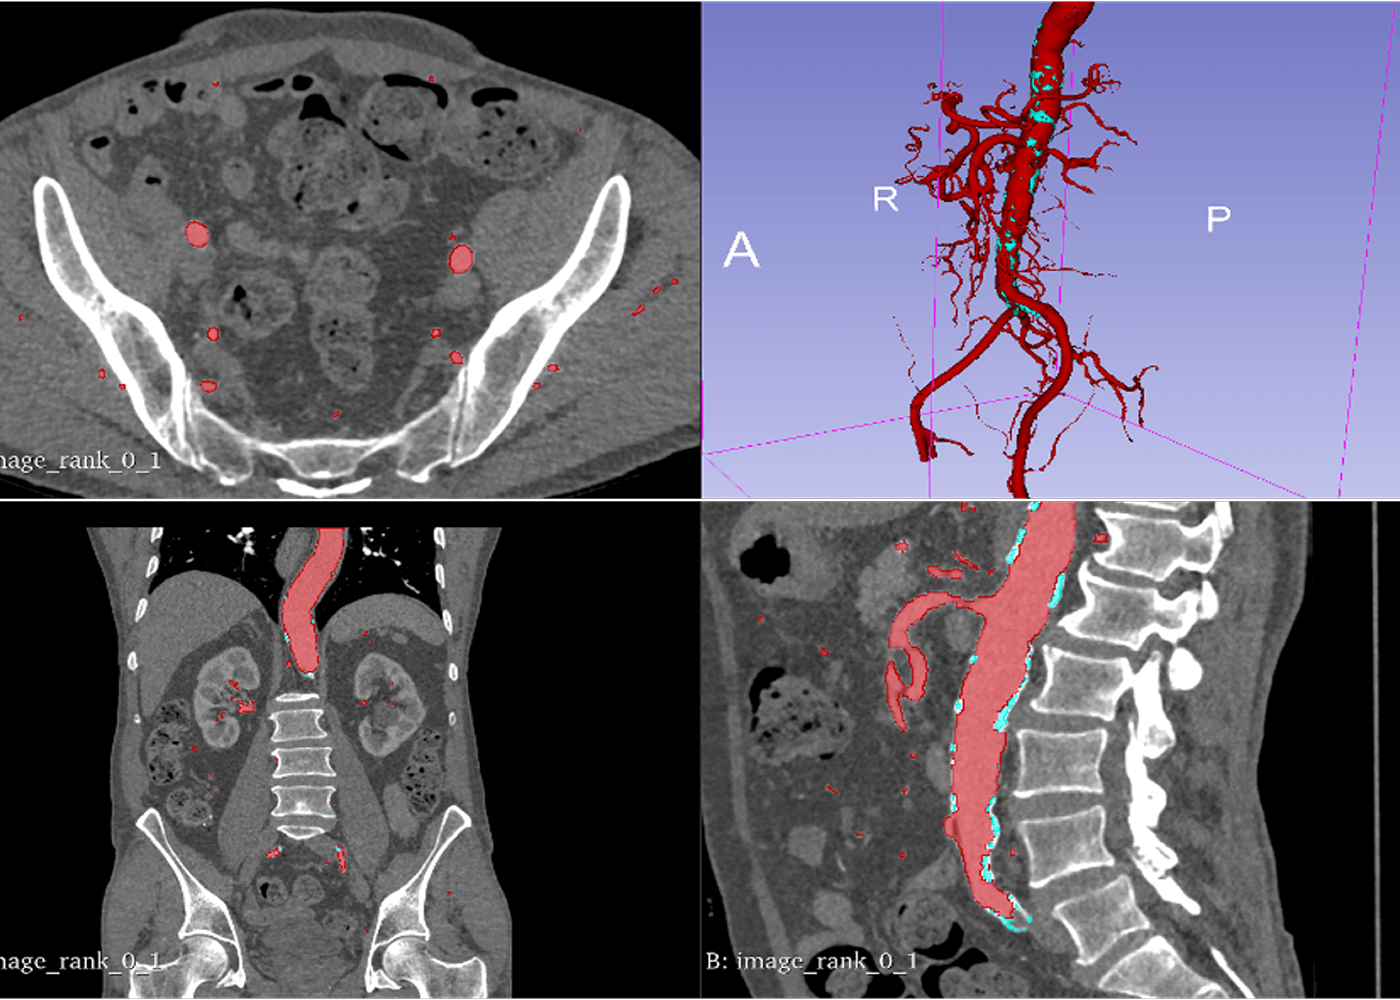

Aorta and all its branches segmentation